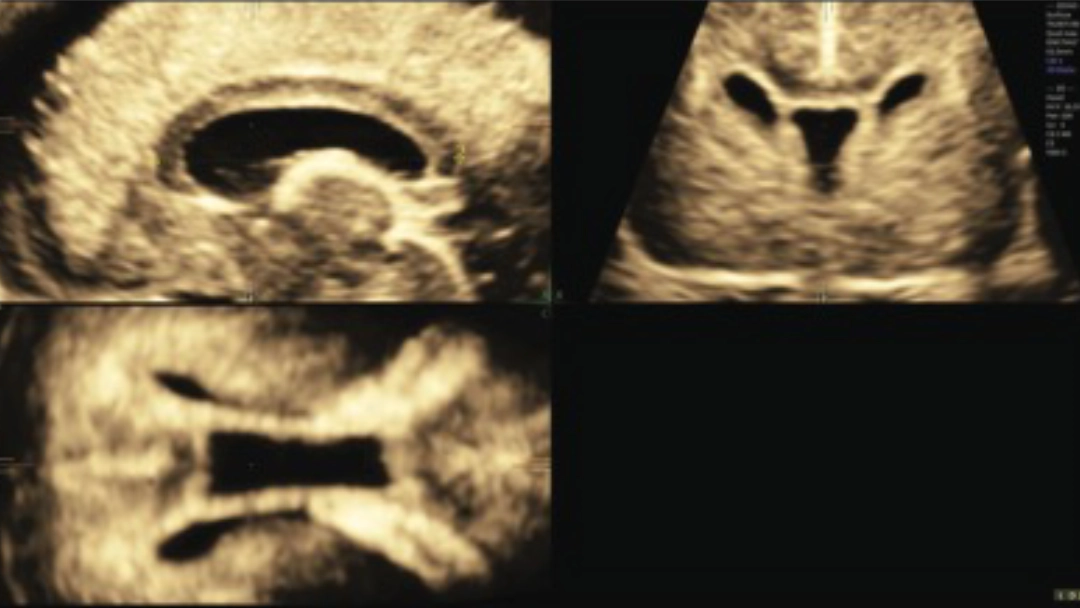

Ejemplo de plano sagital obtenido por ecografía transvaginal 3D, mostrando la medición de la longitud del cuerpo calloso en un feto de 22+3 semanas. Esta alineación precisa fue clave para la calidad y confiabilidad de los datos del estudio.

Las mediciones se realizaron en volúmenes obtenidos solo por vía transvaginal, con alineación exacta del plano sagital a través de imágenes multiplanares. Esto elimina errores de interpretación frecuentes en estudios que usan imágenes transabdominales.